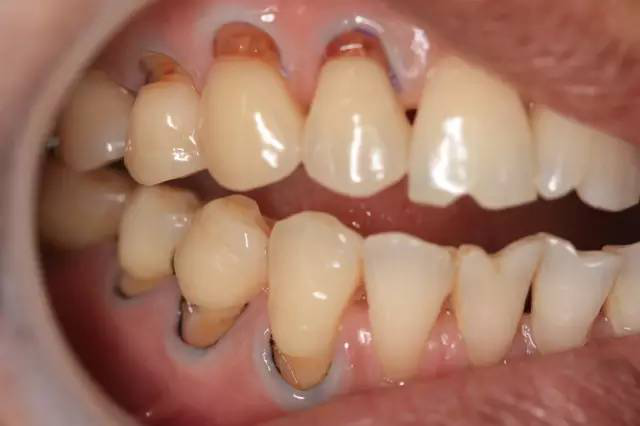

二、不當(dāng)刷牙導(dǎo)致的牙根暴露

長(zhǎng)期橫向拉鋸式刷牙或用過(guò)硬牙刷、刷牙過(guò)猛都會(huì)導(dǎo)致牙頸部磨損,牙頸部是牙齒薄弱部位,因此耐磨能力_差,長(zhǎng)期磨損消耗會(huì)引起牙齦萎縮,牙根暴露,讓我們感覺(jué)牙齒變長(zhǎng)了。

預(yù)防:選擇合適的牙刷,建立正確的刷牙方式,它可以有效的防止牙頸部磨損。

治療:如果已經(jīng)有牙頸部缺損現(xiàn)象的朋友,要及時(shí)將缺損部位修補(bǔ)上,以防繼續(xù)發(fā)展。